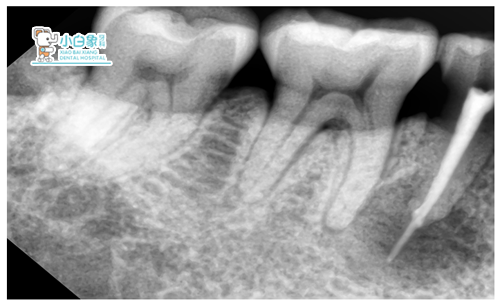

X线示:45根尖区类圆形暗影,边缘骨白线。36根管充填影像,欠填,尖端膨大。

45开髓,揭顶,寻单根管,M3预备后,黄色清亮渗出物,超声荡洗,隔湿干燥,CP引流。36,25常规治疗。

隔日见引流棉存,行根管充填超充。